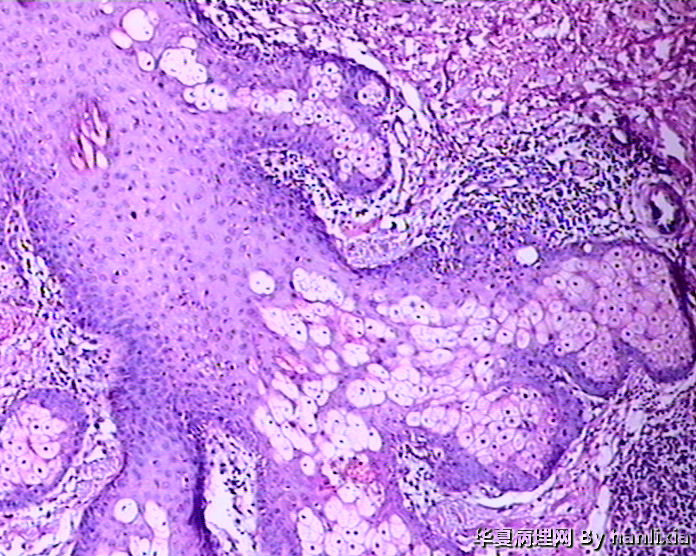

面部皮肤肿物

男性患者,50岁,发现面部皮肤(耳旁)肿物一年余,色黑。

部分区域突破基底膜,应该诊断鳞癌,由日光性角化发展过来的!

AK ,增生活跃,但好像scc不够?

高分化鳞癌可能,也可能AK基础上发展而来的浅表型鳞癌?

高分化鳞状细胞癌